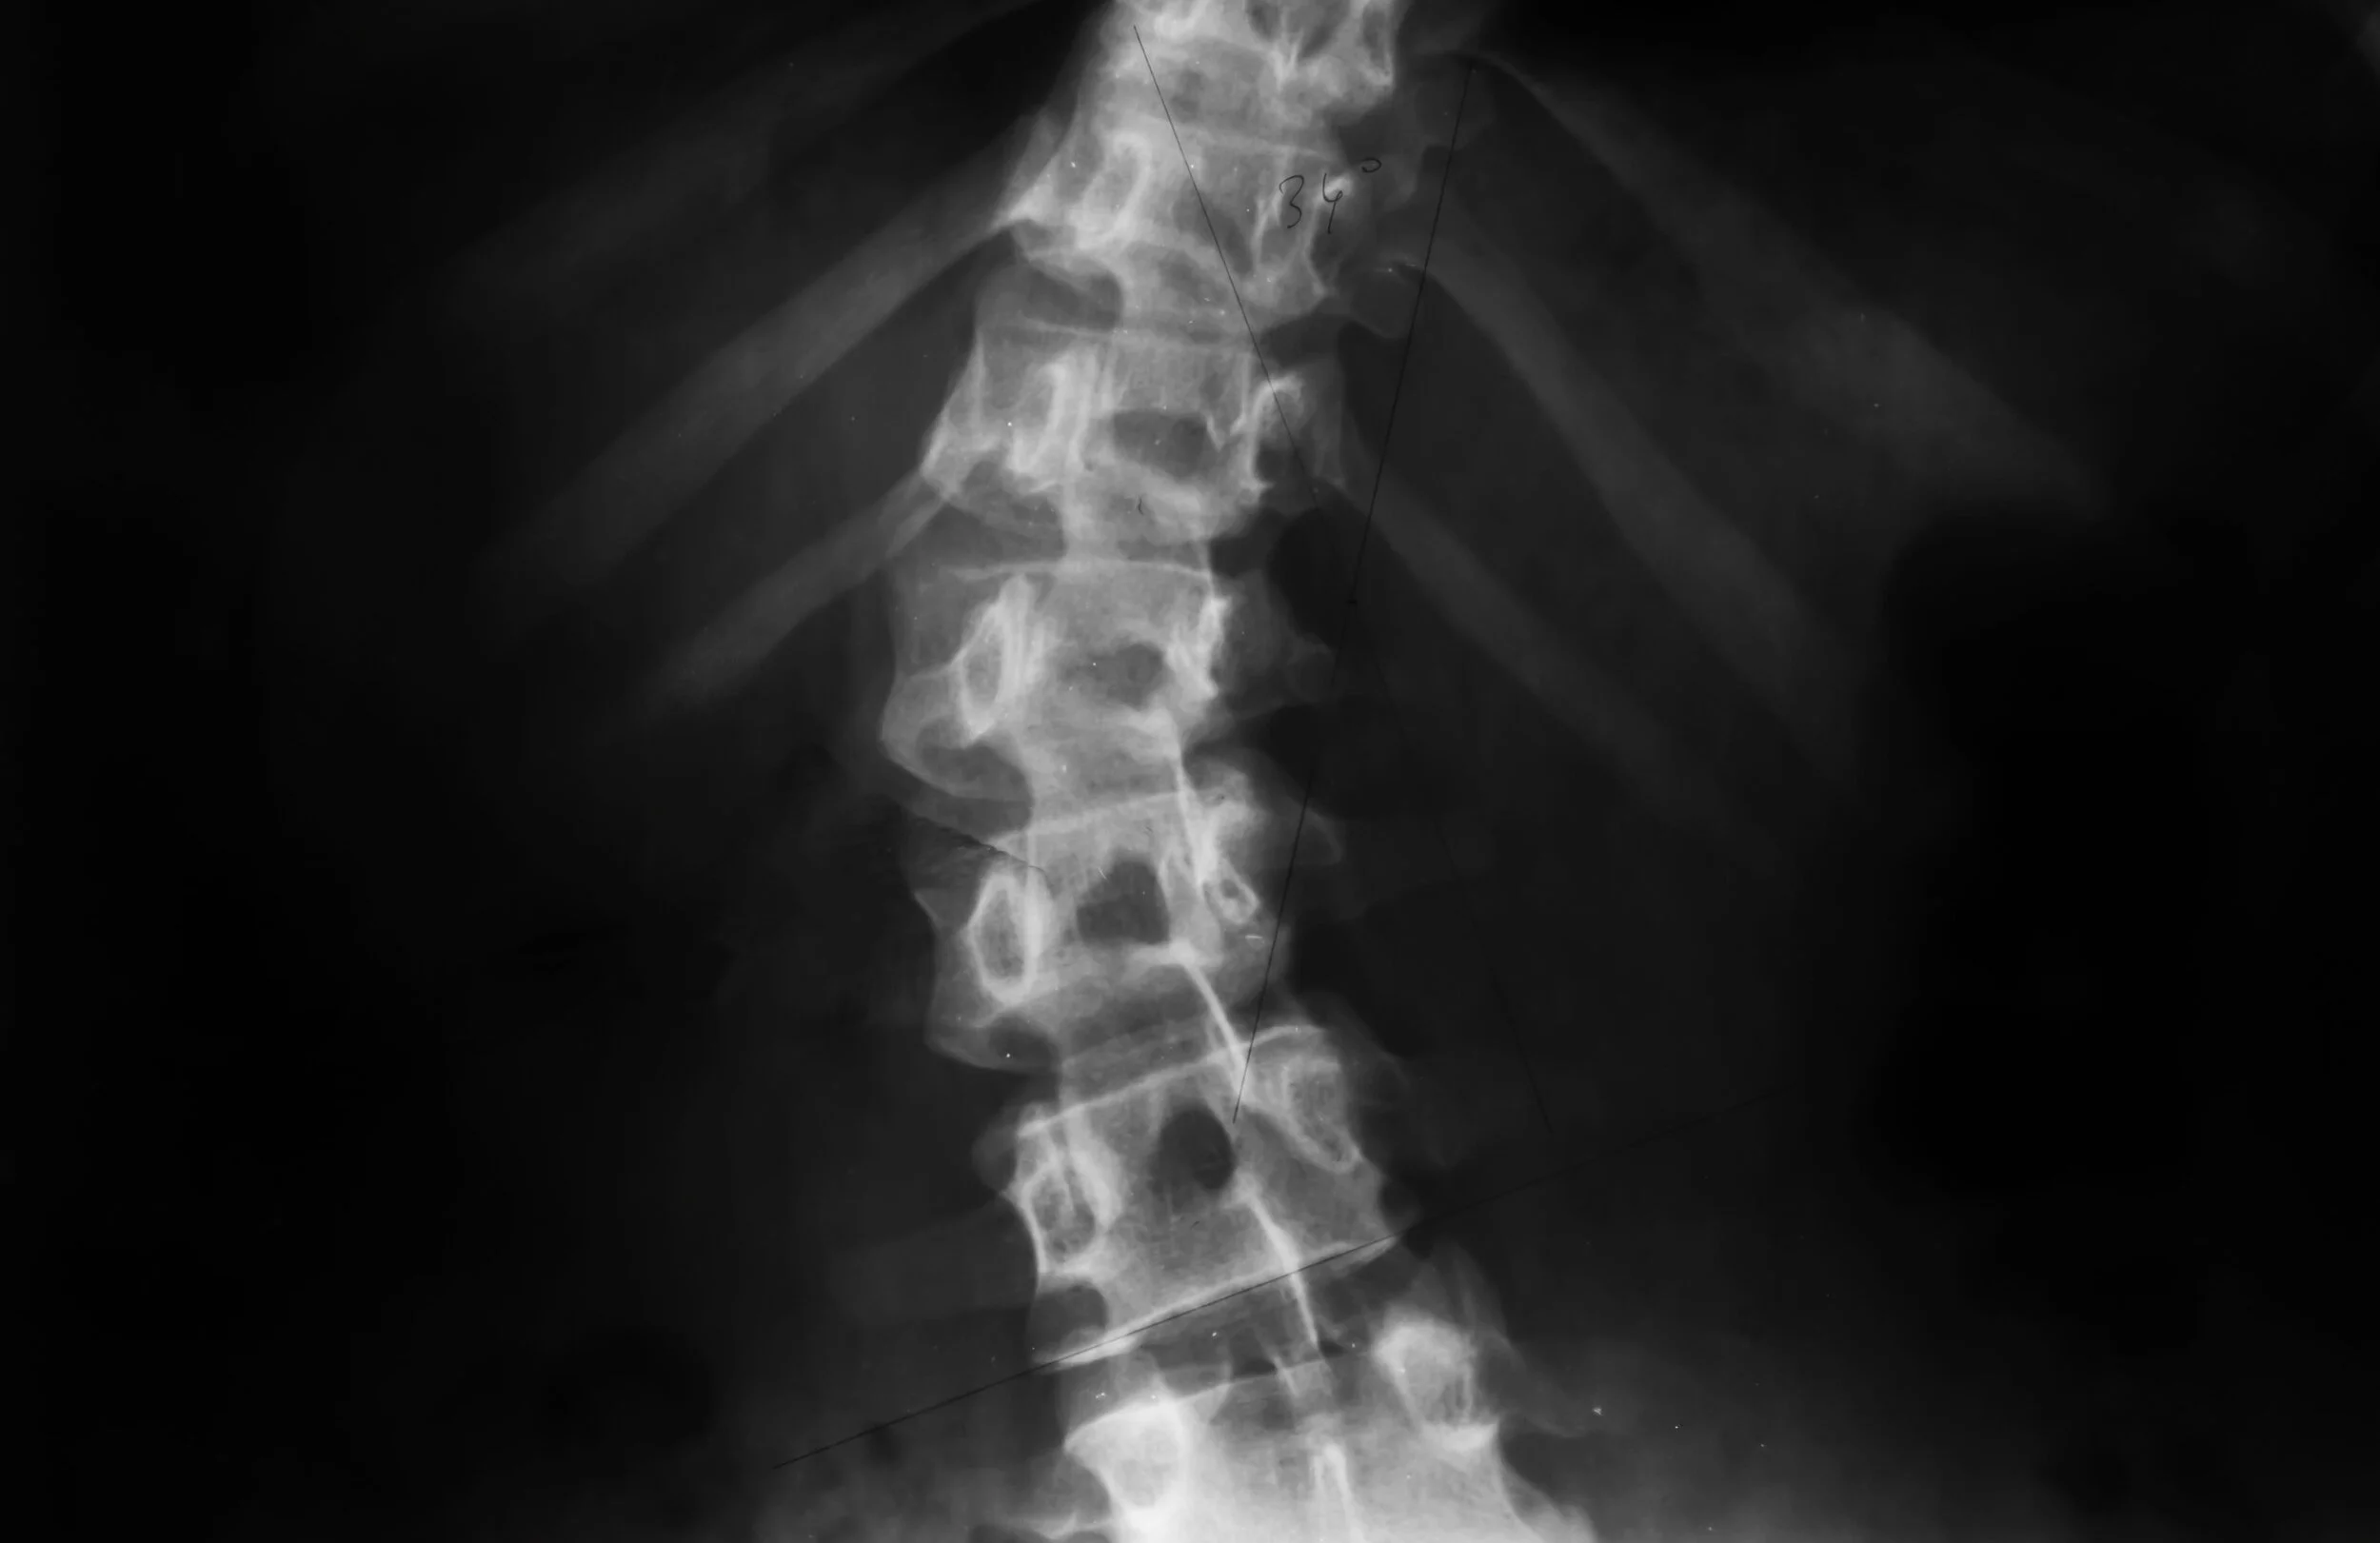

Scoliosis and the Benefits of Chiropractic Care

Chiropractic care may help the scoliosis curve and strengthen the area through specific, safe adjustments. There are also specific guided exercises that can relieve the pain and discomfort caused by scoliosis. If a curve is above a certain percentage, a recommendation may be to consult with Orthopedic for bracing.